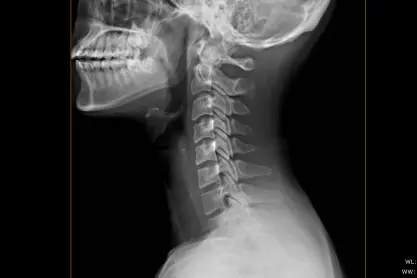

• Spine X-Ray: Assesses the alignment and condition of the spine to diagnose back pain, degenerative disc disease, or spinal injuries.

• Skull X-Ray: Helps diagnose head injuries, sinus issues, or other abnormalities in the skull.